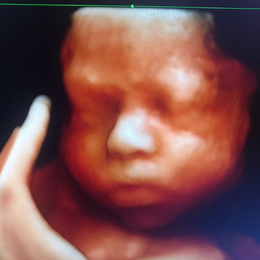

Ecografía del corazón fetal en 4D

En un embarazo normal o de bajo riesgo se recomienda realizarse tres ecografías, una por trimestre. La primera entre las semanas 11 y 14, la segunda entre la 18 y la 22 y la tercera entre la 32 y la 36. Descubre para qué sirve cada una de ellas.